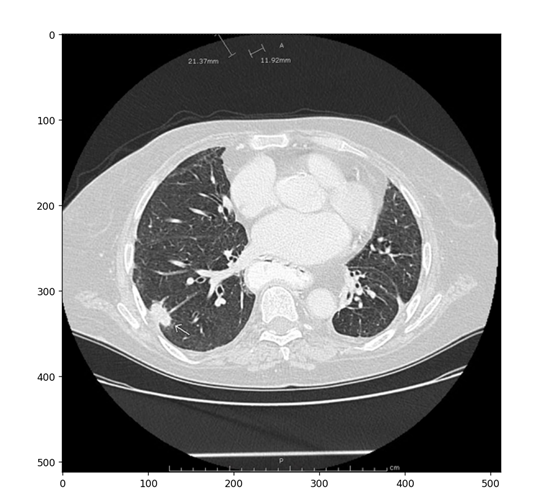

医学图像:

该图片是测试图片,从网站上下载的。